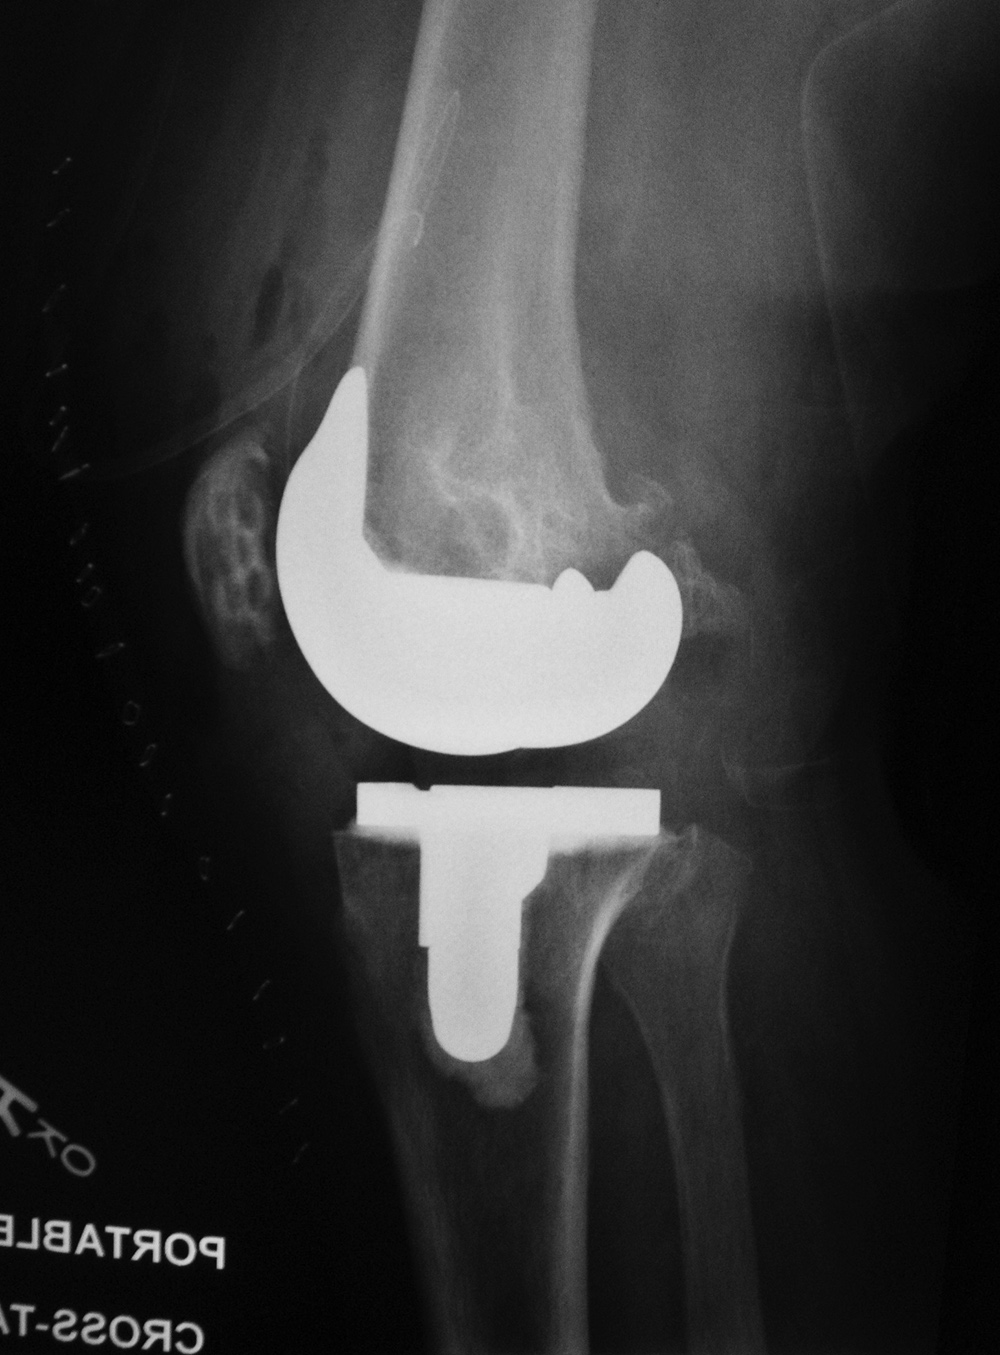

Stryker Triathlon PSC total knee arthroplasty

- posterior cruciate removal prosthesis |

| There is a postoperative drain and skin staples. From Taljanovic, 2005 |

There is also a surgical drain and skin staples in place. 65 year-old woman. |